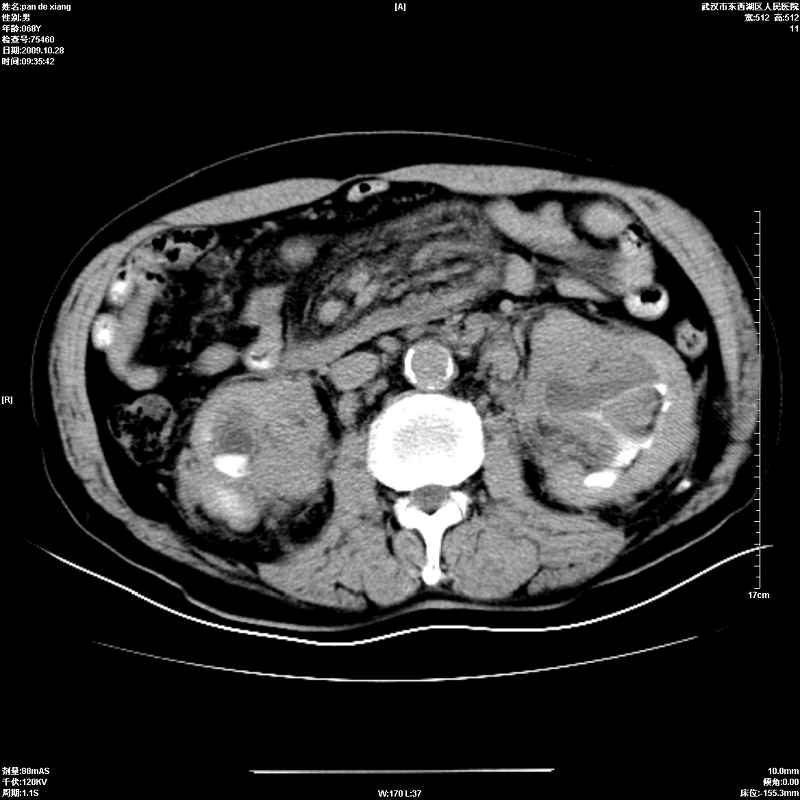

以下是引用杀毒软件在2009-10-28 20:41:00的发言:[br]结合临床考虑---白血病双肾改变或淋巴瘤。

以下是引用zxl51642在2009-10-29 9:59:00的发言:[br]结合临床“单克隆免疫球蛋白血症”,考虑双肾为继发损害并肾功能不全(尿中大量igg及少量iga、igm等大分子免疫球蛋白滤出所致继发损害),椎前软组织肿块为髓外造血。与浆细胞瘤有区别,平扫时有战友说的很清楚。